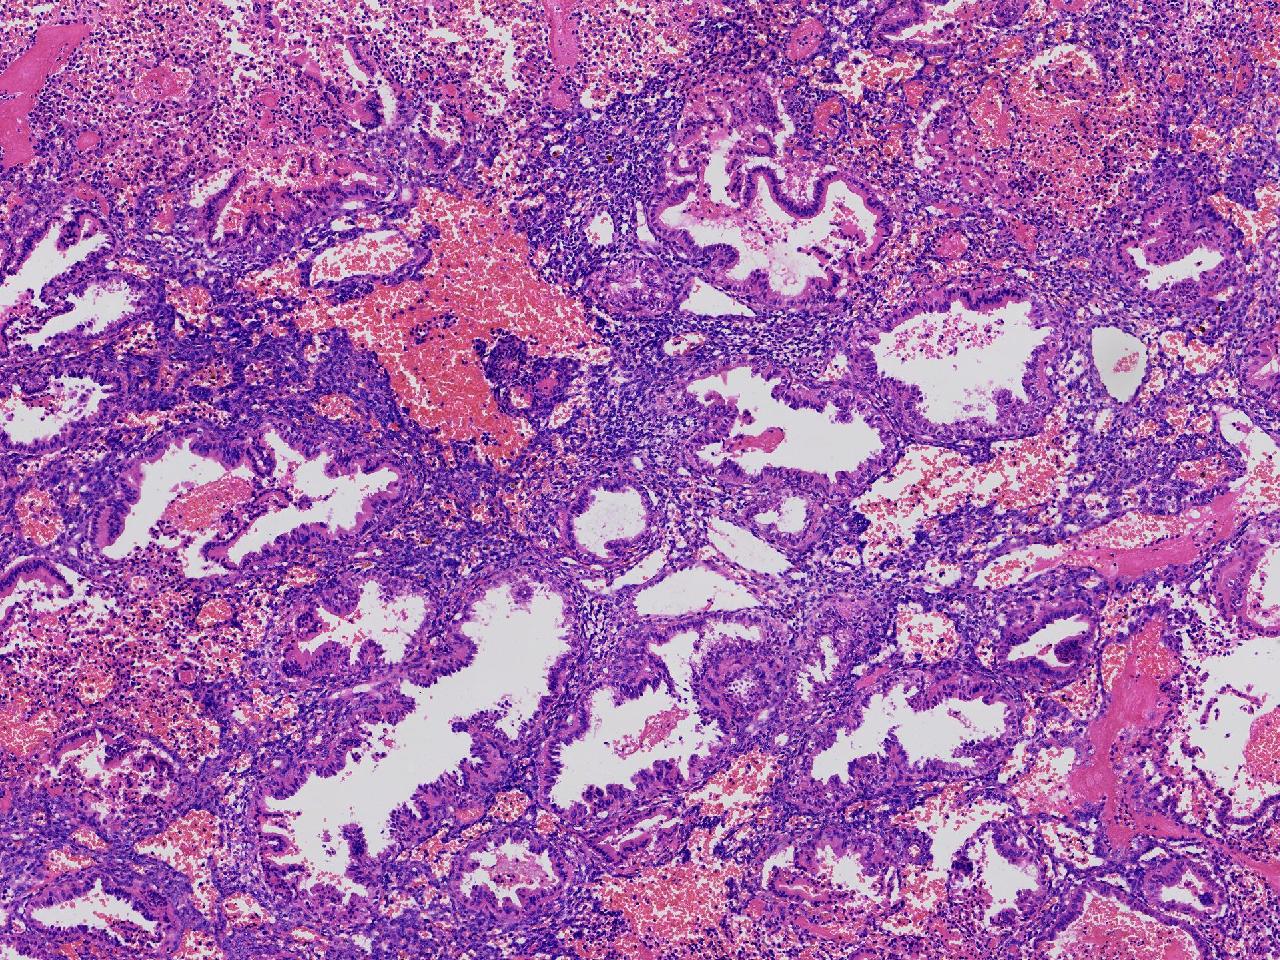

性别

女

年龄

45岁

临床诊断

阴道不规则出血20余天,

一般病史

彩超示:宫腔内见约41X11毫米的不均质回声区。宫腔镜示:宫腔形态正常,内膜粉红,不规则增厚。

标本名称

子宫内膜

大体所见

灰粉色不整形软组织多块,1.5X1X0.6厘米。

分泌反应子宫内膜,伴有出血。

晚泌期及月经早期改变,局部呈啫酸性乳头状化生改变。